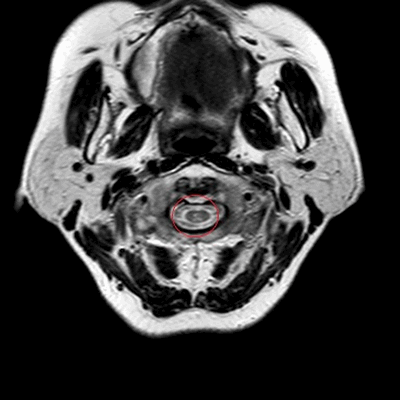

МРТ шеи: миелопатия (аксиальная плоскость, Т2 ВИ)

- психо-эмоциональная нестабильность - проявляется плаксивостью, резкими перепадами настроения, бессонницей, апатией, депрессивными расстройствами и пр.;

- гипертонические кризы, устойчивое к медикаментозной терапии повышение артериального давления;

- выявленные изменения в головном мозге предположительно связанные с патологией сосудов шеи;

- нарушение контроля функций тазовых органов;

- предоперационная диагностика;

- контроль изменений в динамике на фоне лечения.